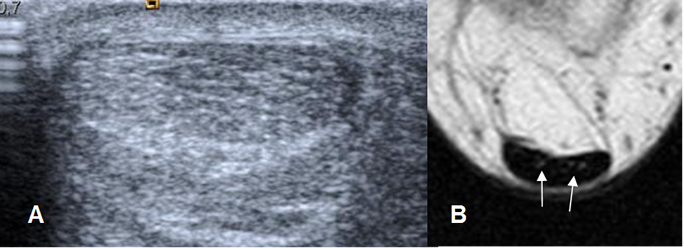

Fig 19. Fascia plantar normal.

A y B: RM axial en T1 y C: RM coronal en T1. Rama medial (Flecha delgada), central (Flecha gruesa) y lateral (Cabeza flecha).

Fig 20. Fascia plantar normal.

A: RM sagital en T2 y B: RM sagital en STIR. Estructura hipointensa en todas las secuencias.

Fig 21. Fascia plantar normal en ecografía, corte sagital.